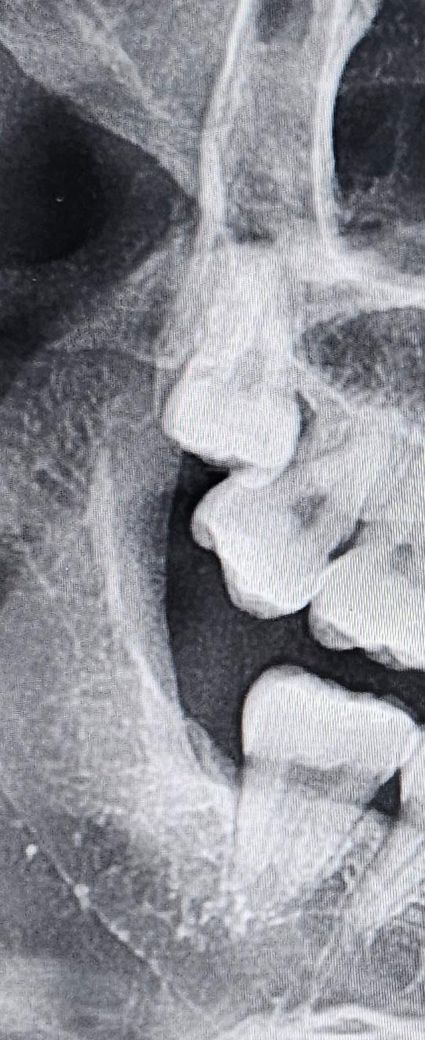

사랑니 이거 뽑기 어려운 애일까요??

오른쪽 위에인데

이 사망니 놈 뽑기 힘든 난이도 높은 애일까요?

위쪽 사랑니는 발치가 어렵지 않지만 사진에 보이는건 앞치아에 걸려 잇어서 잇몸도 절개를 하고 잇몸뼈도 삭제를 하셔야될것같습니다.

상악 완전 매복 치아의 경우에는 하악 만큼 난이도가 높습니다. 또한 입이 잘 벌어지지 않거나 coronoid proc. 등이 걸리는 위치라면 발치 난이도가 많이 높아질 수 있습니다. 물론 해당 치아가 어느 방향으로 나타나고 있는지가 더 중요할 것으로 보이며 ct 촬영이 필요합니다.

네 난이도가 꽤 높습니다. 옆 치아와 겹쳐있기 때문에 온전히 빼기 어려울 수도 있습니다..